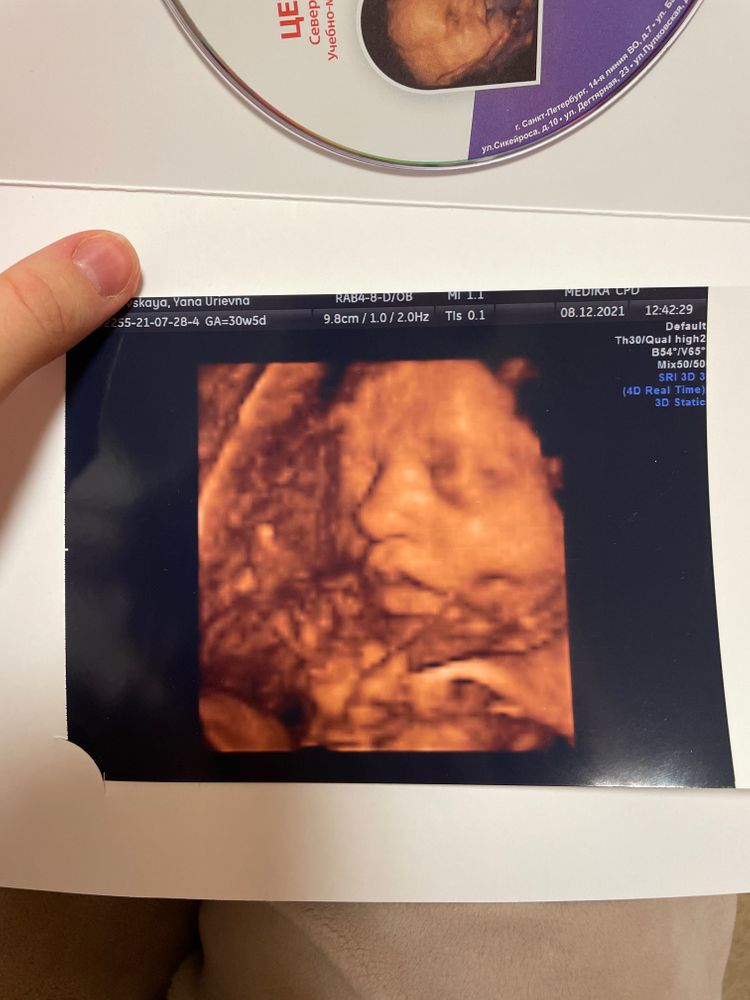

Мое маленькое чудо 💖💖💖 3-ий скрининг + фото

УЗИ, КТГ, доплерНаступила 32-я неделя моей беременности.

Практически ничего не беспокоит, вес не летит, кости не болят , малышка шебуршит и икает) По узи все хорошо, без отклонений, растем и развиваемся ✨ Она стала уже такой большой)) сняли видео, показали волосики в водах)) мохнатая вся в мужа)) сразу открыла глаза начала осматриваться, почувствовала что-то неладное))) запихивала руки и ноги в ротик, закрывалась) такая смешная, жду не дождусь, когда смогу тебя увидеть и подержать на ручках 🥺🥰

Срок 30,5 - вес 1500-1600гр.